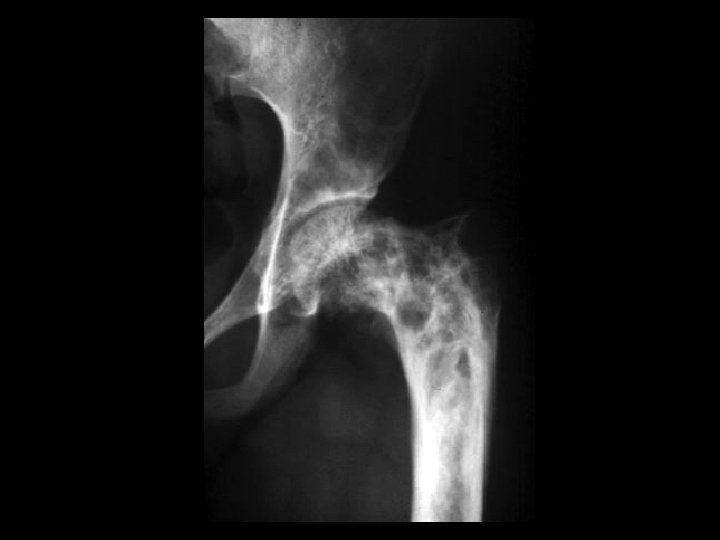

Severe OA & Geode • Findings: – severe osteoarthritis of the right hip – lytic lesion in the adjacent superior acetabulum – hot on bone scan • ddx: – fibrous dysplasia – ABC – infection – erosion